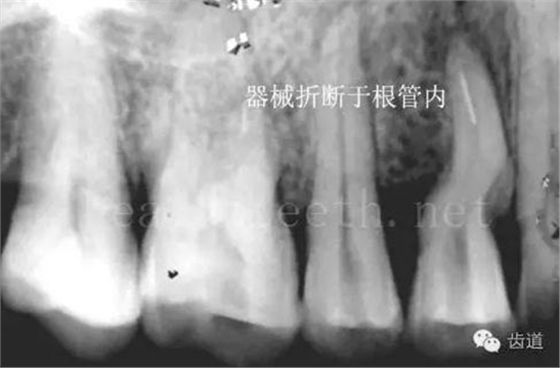

因?yàn)楸旧聿桓阏衬げ。占降牟±邢?,大多是同事收?/span> 頰粘膜扁平苔蘚 舌粘膜扁平苔蘚 舌緣創(chuàng)傷性潰瘍 長期戴活動義齒不當(dāng)或是戴不良修復(fù)義齒造成的口腔粘膜潰瘍,應(yīng)該引起高度警惕,因?yàn)檫@種潰瘍?nèi)菀装┳?/span> 黑毛舌 舌息肉,該患者同時伴有胃、食管息肉,后來看內(nèi)科了,具體情況不詳 四、孩子的牙齒問題 乳牙未退,牙根穿出牙齦對上唇粘膜造成刺激 乳牙滯留,也是孩子在退牙過程中最容易遇到的問題 五、牙齒發(fā)育上的問題 變色牙 氟斑牙 釉質(zhì)發(fā)育不全 四環(huán)素牙 牙神經(jīng)治療后的牙齒變色 10歲孩子剛剛萌出的牙齒變色 2、埋伏牙 左上乳3滯留,恒3未見萌出,曲面斷層片顯示牙齒埋伏 通過CT片確定埋伏牙齒具體的位置,顯示距離左側(cè)上頜竇很近,偏唇側(cè),這為手術(shù)定位提供了方便 手術(shù)中切斷、完整拔出,未損傷上頜竇 其他埋伏牙 3、多生牙 病例1 病例2 病例3,同時多生兩顆牙齒 4、各種畸形牙 畸形過小牙 融合牙:恒牙和乳牙都可以發(fā)生融合的情況(兩顆牙齒長在了一起) 畸形中央尖:在牙齒的中央,兩個牙尖之間又多長出一個牙尖,由于進(jìn)食的磨耗很容易造成磨穿,神經(jīng)就會與外界相通,出現(xiàn)牙髓炎的癥狀 六、牙齒的外傷 牙冠折斷 牙根折斷 烤瓷牙打樁修復(fù)后牙根折斷 外傷后牙齒的全脫位,應(yīng)該保留牙齒盡早做再植手術(shù) 七、牙齒的慢性損傷 牙頸部楔狀缺損 牙冠劈裂及完整拔除后的情況 牙根縱裂及拔除后的情況 牙隱裂,牙齒表面有肉眼看不到的裂紋,細(xì)菌通過其進(jìn)入牙髓,容易出現(xiàn)牙髓炎癥狀,嚴(yán)重可以造成牙齒的劈裂 這是一位來中國學(xué)習(xí)的俄羅斯大學(xué)生的牙齒,已經(jīng)做過了根管治療,牙齒咬合面有隱裂,通過鋼絲結(jié)扎固定,做鑄造金屬冠修復(fù)。 八、牙髓炎、根尖周炎 下面圖片都是慢性根尖周炎的病例,有了齲齒,進(jìn)一步發(fā)展就是牙髓炎,如果此時沒有得到及時的治療,疾病會逐漸發(fā)展破壞到根尖的骨質(zhì),將骨質(zhì)破壞后就在牙齦上出現(xiàn)一個膿瘺,此時患者不再感覺到牙齒的疼痛了,往往忽視了治療,但是這種不痛并不是疾病好轉(zhuǎn)了,而是因?yàn)榧膊〉难仔詽B出得到了引流,這個膿瘺會出現(xiàn)有時候變大了,有時候又變小了,但是如果不治療是不會自己愈合的,只有經(jīng)過完善的根管治療后才有好轉(zhuǎn)的可能,但是在疾病的治療中時間是起決定作用的,時間拖得越晚,好轉(zhuǎn)的可能性越小,經(jīng)過根管治療后如果膿瘺還是沒有消失,就需要做根尖刮治術(shù),如果仍然沒有好轉(zhuǎn),就只能做根尖切除術(shù)了,這對牙齒的穩(wěn)固是不利的。下面圖片中在膿瘺中插入了一個牙膠尖,是我們做根管充填用的材料,是非常軟的,就是在口腔牙齦瘺管的地方插進(jìn)去,通過拍牙片可以清晰地看到它到達(dá)的位置,從而確定發(fā)病的牙齒,此處是為了讓大家看得更清楚。 門牙兩個膿瘺 烤瓷牙修復(fù)后牙齦出現(xiàn)兩個膿瘺,插入牙膠尖,牙片顯示牙膠尖到達(dá)的位置就是根尖炎癥的位置,根尖骨質(zhì)密度降低(發(fā)黑的地方) 牙齒根尖膿瘺,治療前、中、后的圖片對照,完善根管治療后膿瘺明顯消失了 牙髓炎和根尖炎治療的關(guān)鍵就是根管治療 合格的根管充填治療 不良的根管充填治療 九、關(guān)于智齒(第八顆牙) 四顆長不出來的智齒 智齒反復(fù)發(fā)炎造成的頰瘺,膿腫切開引流后面部會留疤 智齒造成的頜骨囊腫,手術(shù)切除后需要植骨 十、各種錯合畸形 開合 深覆合 深覆蓋,上頜前突 反合(地包天) 牙齒排列擁擠 來源:牙醫(yī)愛看的 KQ88口腔醫(yī)學(xué)網(wǎng)